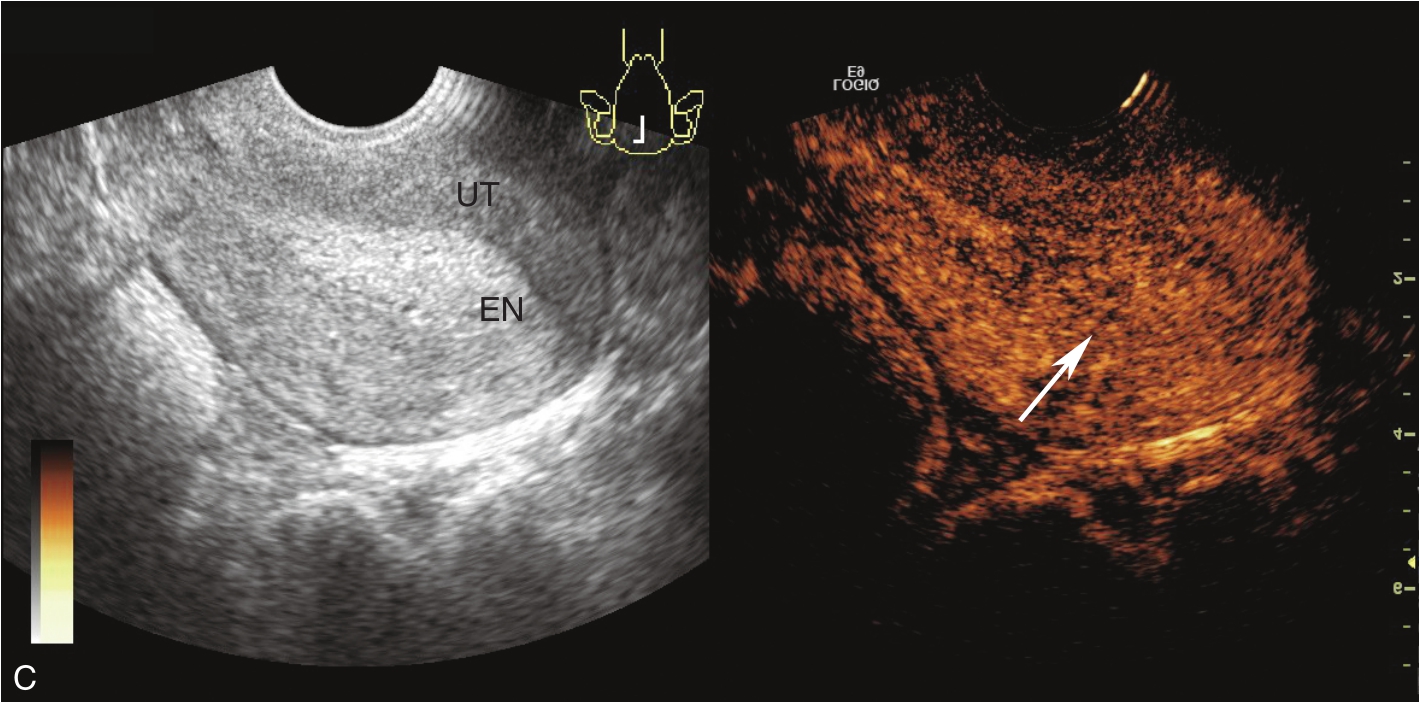

经阴道超声检查见图3-5-1。子宫后位,宫体大小约5.8cm×5.0cm×5.1cm,宫内膜厚约0.75cm(单层),内膜回声不均匀。宫腔未见分离。宫壁回声均匀。内膜内见多个囊性结节,较大者大小约0.5cm,内透声可。CDFI:未见异常血流信号。双侧附件区未见异常回声。盆腹腔未见明显积液。超声检查结果:宫内膜增厚伴回声不均匀。

图3-5-1 常规超声声像图

A.后位子宫的矢状切面(经阴道),子宫内膜增厚,单层厚约0.75cm,内见多个小暗区;B.后位子宫的横断面(经阴道);C.后位子宫的矢状切面(经阴道),彩色多普勒能量图超声检查显示子宫未探及明显血流信号;D.右卵巢;E.左卵巢。UT:子宫;EN:子宫内膜;R-OV:右卵巢;L-OV:左卵巢。

经静脉超声造影见图3-5-2及ER 3-5-1。注入造影剂后14s,子宫肌层开始增强(图3-5-2A箭头所示);子宫内膜始增时间约注入造影剂后21s,从周边开始增强(图3-5-2B箭头所示),晚于子宫肌层,向心性充填;注入造影剂后40s,内膜造影剂达峰,造影剂分布较均匀,呈等增强(图3-5-2C箭头所示);注入造影剂后73s,宫内膜晚于肌壁清退(图3-5-2D箭头所示);TIC曲线显示内膜呈晚增强、等增强、晚清退(黄色曲线代表内膜,绿色曲线代表子宫肌层)(图3-5-2E)。

图3-5-2 经静脉超声造影声像图

A.注入造影剂后14s;B.注入造影剂后21s;C.注入造影剂后40s;D.注入造影剂后73s;E.TIC曲线。UT:子宫;EN:子宫内膜;A、B、k、C:拟合曲线方程式的系数;MSE:均方误差;TtoPk:达峰时间;Area:曲线下面积;Grad:梯度;ATm:到达时间;TI:时间强度。